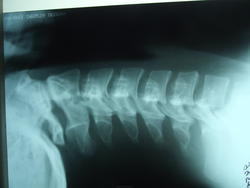

Получил травму.Не нравится атлант. Коллеги, помогите разобраться.

К сожалению не могу., есть предполодение про аномалию Кимерле

Нет, тут нет аномалии Кимерли.

Аномалия Кимерли- дополнительная костная дужка первого шейного позвонка, которая нередко  сдавливает позвоночные артерии, питающие головной мозг кровью; на представленных  Вами рентгенограммах эта мальформация не определяется. Ссылка по теме:

Согласна, никакого Кимерли нет.

Что за изогнутая костная дуга? (стрелками - одна, там же есть и вторая).